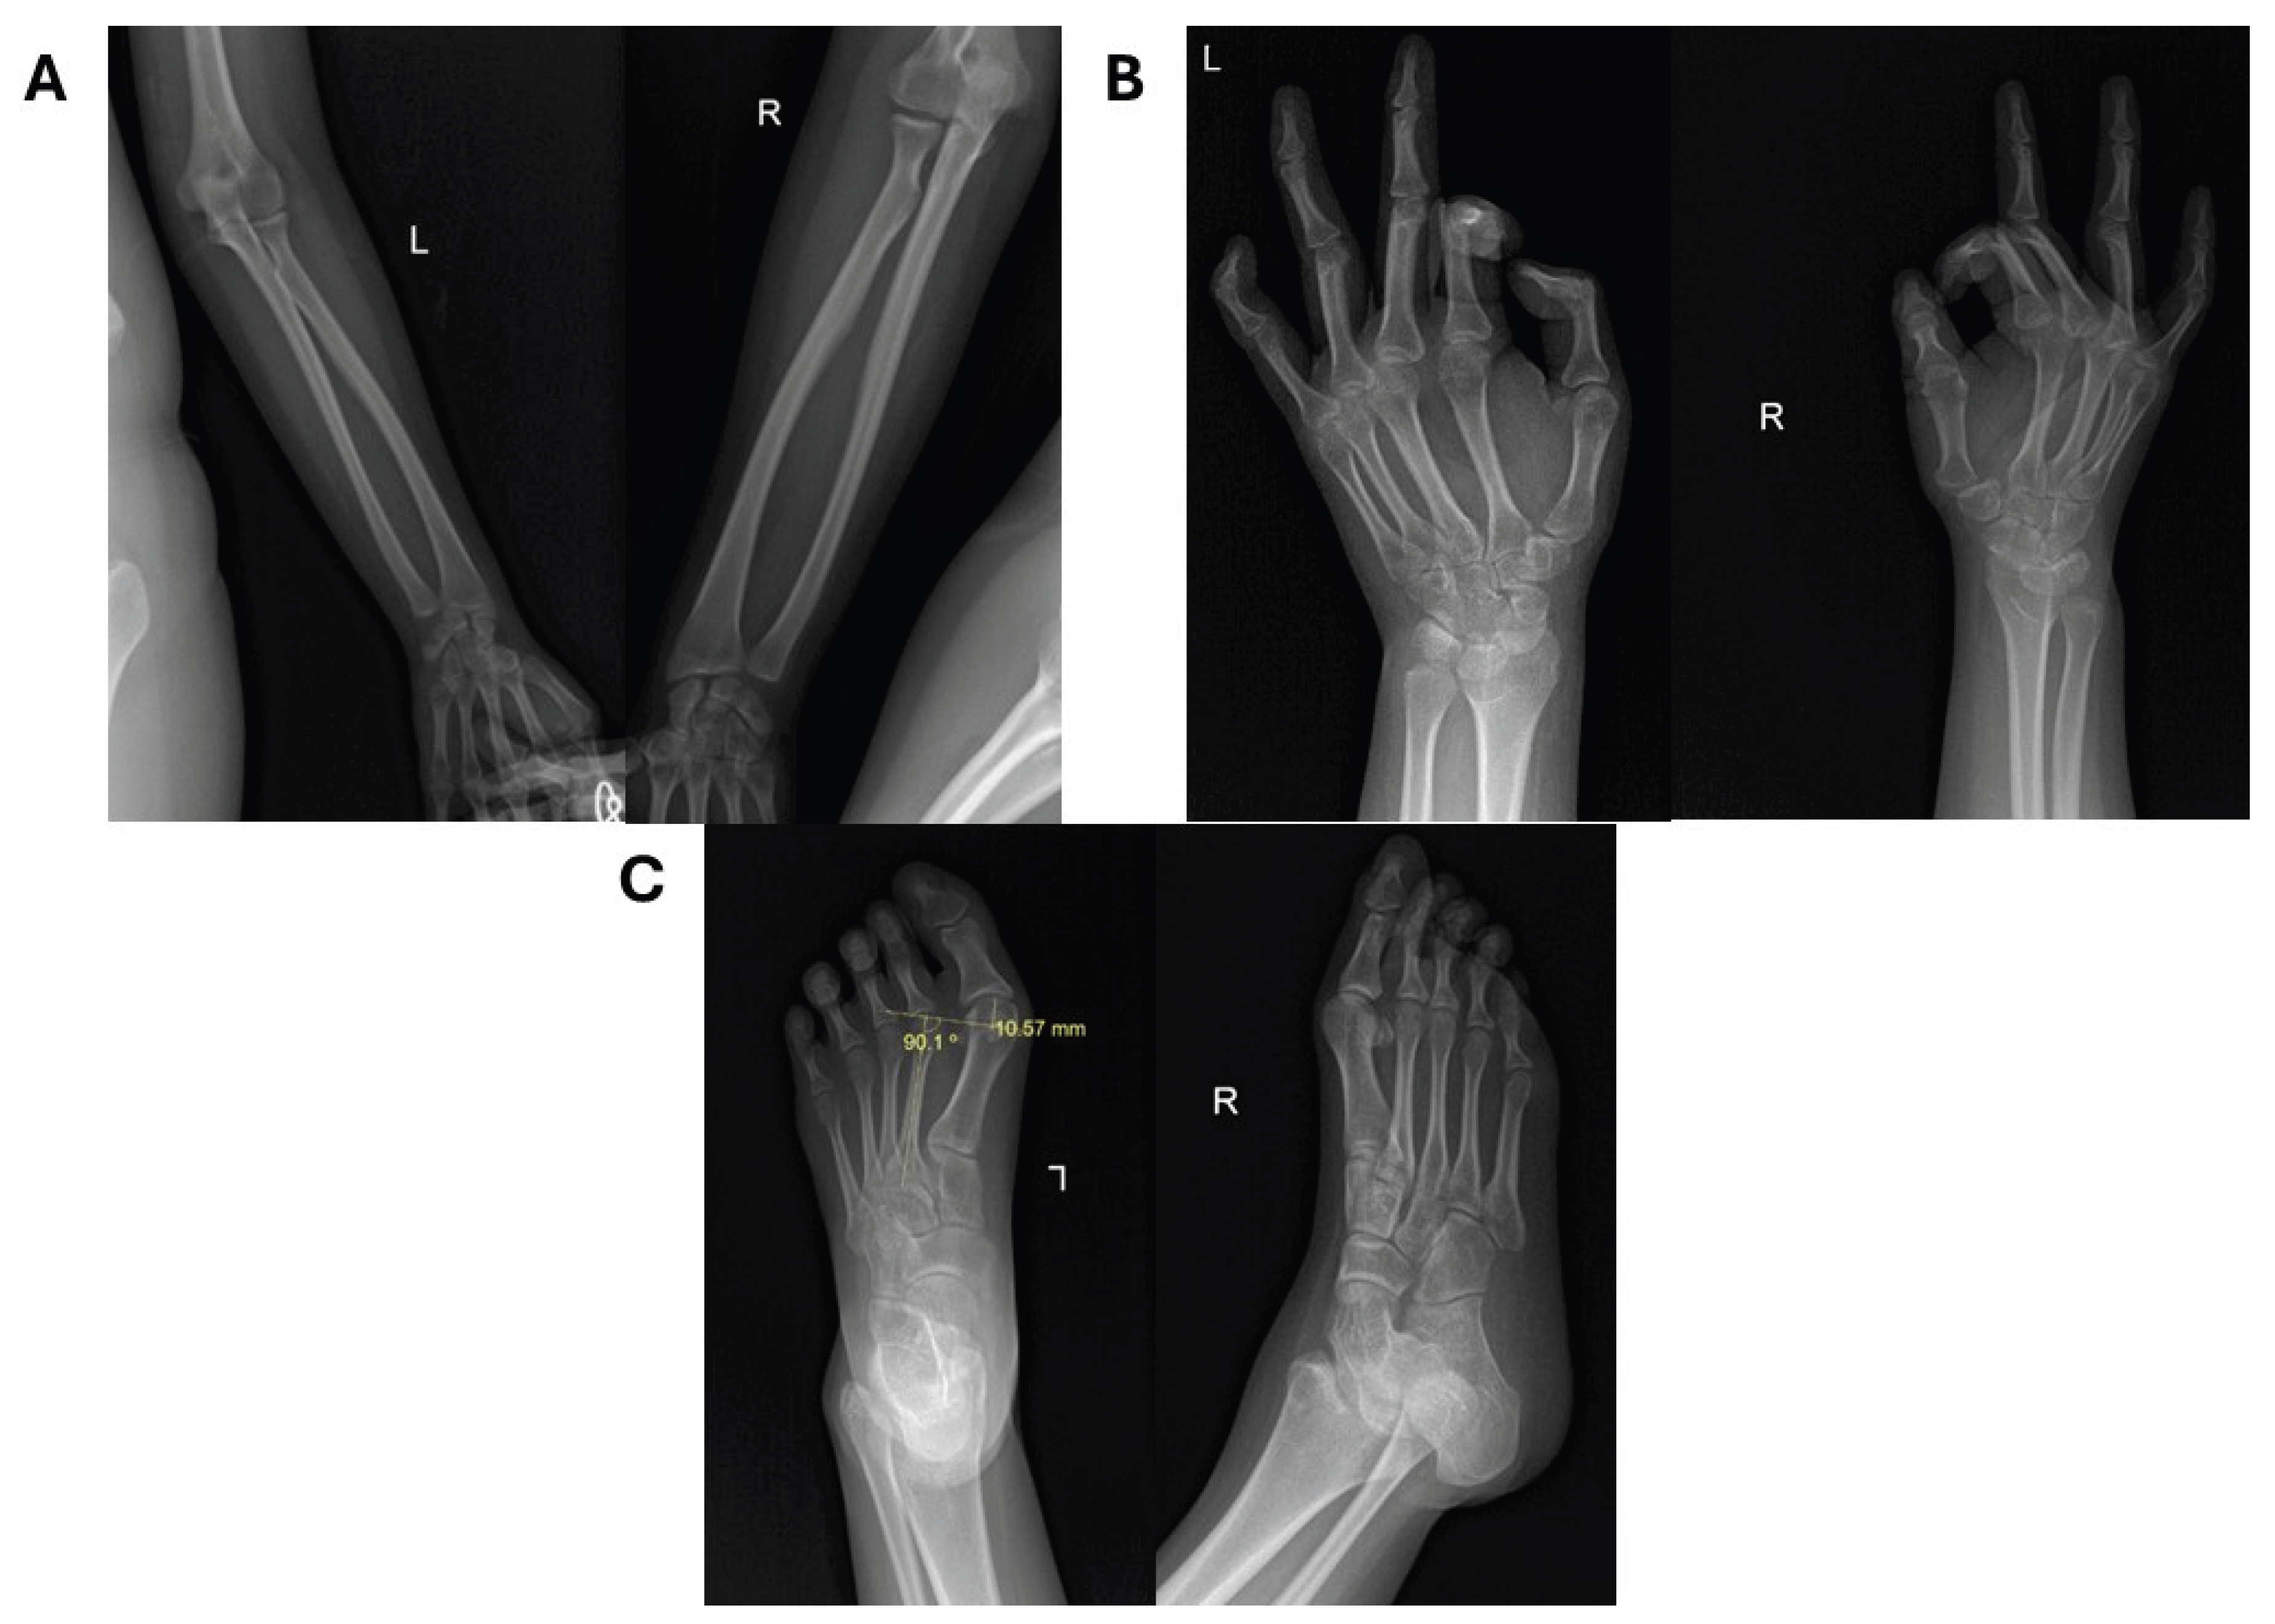

| SBBYS-type Ohdo syndrome | KAT6B | Intellectual disability, blepharophimosis, ptosis, long thumbs, dental anomalies | Hallux valgus, scoliosis, normal patellae, shortened phalanges, ulnar variance |

- KAT6B-related disorders such as Say-Barber-Biesecker-Young-Simpson (SBBYS) syndrome can be differentiated from genitopatellar syndrome by key skeletal findings, such as the presence or absence of patellae and characteristic craniofacial and digital anomalies.

- The presence of subtle but specific hand and foot anomalies, such as long thumbs, single palmar crease, and bilateral hallux valgus, can offer early diagnostic clues in syndromic intellectual disability, even before genetic confirmation.